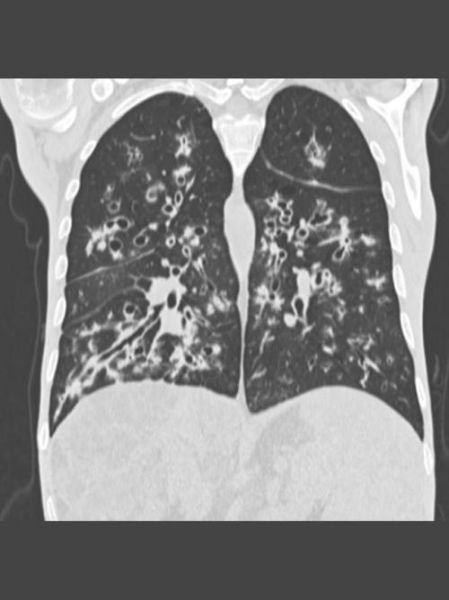

(图片来源网络,侵删)